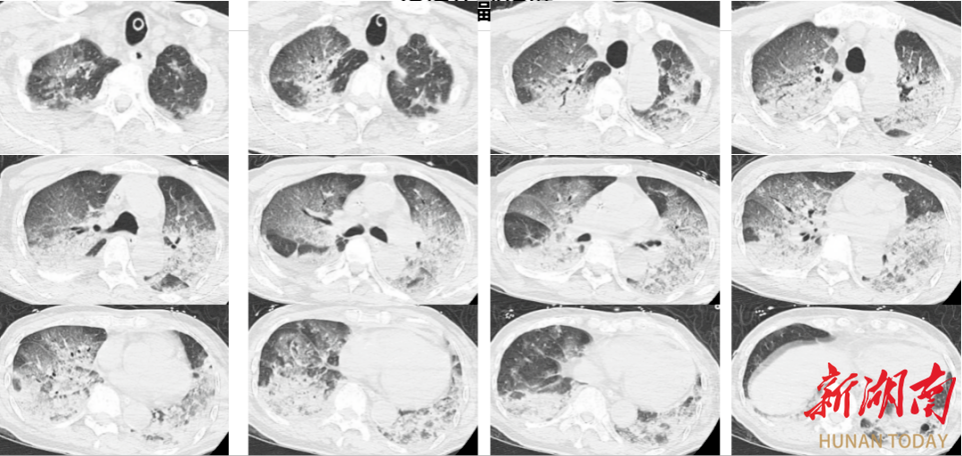

入院时,韩爷爷意识不清,血压、心率下降,医生随即为他安排头颅、胸部CT和肺血管CTA检查,结果显示,老人的双肺出现大面积白色影像。经会诊,韩爷爷被确诊为热射病诱发的肺水肿。

图源:潮新闻